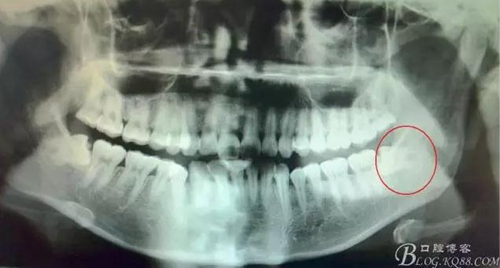

患者、李xx、女、20歲,主訴:左側(cè)下后牙牙齦不適數(shù)天。??茩z查:38水平位、牙冠萌出黃豆大小,頰側(cè)牙齦未見明顯紅腫,全景片檢查:38水平位、雙根、分叉大,37遠(yuǎn)中頸部未見齲壞。診斷:38中位水平阻生 治療計(jì)劃:微創(chuàng)拔除38。術(shù)前與患者充分溝通,告訴患者采用無痛sta阻滯麻醉加不切開翻瓣拔除。患者同意手術(shù)方案,簽知情同意書。

圖1.全景片檢查:38水平位、雙根、分叉大。